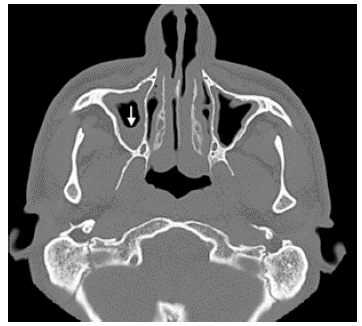

Paranasal sinus tomography with thickening of the mucosal lining, partially occupied by a soft tissue density mass.

Figure 3: Paranasal sinus tomography with thickening of the mucosal lining, partially occupied by a soft tissue density mass.

Source: Document obtained during the study.

After finding dextrocardia, it was necessary to ascertain visceral situs (normal, inverted, ambiguous). A simple tomography documented pulmonary bronchiectasis, as well as liver on the left side (Figure 4), leading to suspect KS; this was confirmed with findings of chronic sinusitis in paranasal sinus tomography. In addition, HRCT showed tomographic signs of infectious bronchiolitis.

Both sinus radiographs and CT scans of patients with KS may show thickening of the mucosa, opacified paranasal sinuses and hypoplastic frontal sinus.